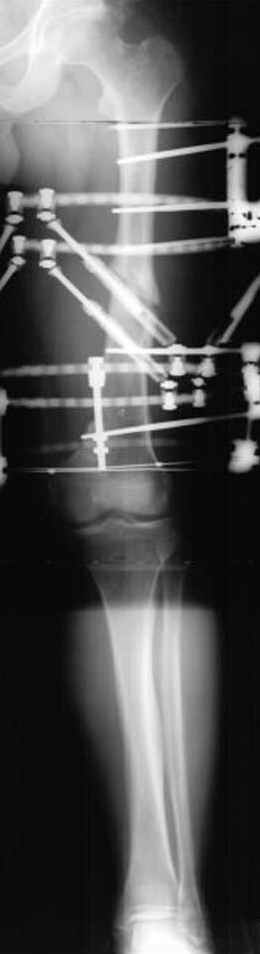

Несколько снимков из моей коллекции, чтобы разьяснить, почему мы до сих пор делаем различные варианты остеотомии.

На рисунке N1 предоперационный план лечения ложного сустава шейки бедра- линия ложного сустава, угол и направление введения импланта, клиновидная остеотомия в градусах и миллиметрах, второй снимок после коррекции, расчет, на сколько удлиняется конечность и размеры импланта;

N3 рисунок окончательный снимок, после операции моя рентгенограмма должен выглядеть примерно как эта картина. На N4 снимке клин перед удалением; N5 послеоперации 3 нед.; N6 окончательная рентгенограмма.

пластическая модель; и коррекция бедра аппаратом Илизарова.